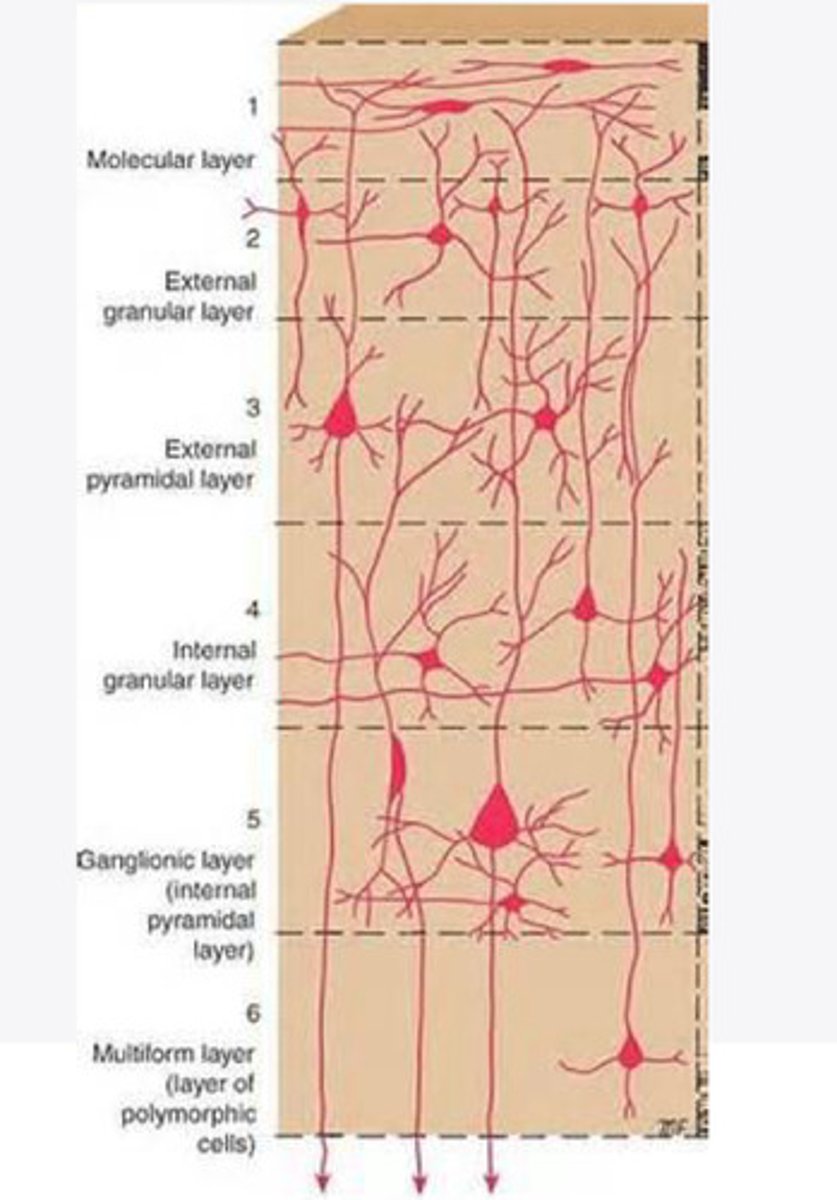

divided into 6 distinct layers, due to varying densities of cell body types within each layer

The cortex of the brain is divided into how many layers? Why is it divided into layers?

Layers of the cortex of the brain pic

2 and 4

What are the layers of the cortex that are associated with input?

3 and 5

What are the layers of the cortex that are associated with output?

molecular layer

What is the name of Layer 1 of the cortex of the brain?

very few cells

Does Layer 1 of the cortex have a lot or few cells?

receives dendrites from internal layers so it may actually function as a coordinating center where layers can communicate action

What does Layer 1 of the cortex do?

1

Every layer sends densities to Layer ____?

1

What layer serves as the "water cooler" of the brain?

external granular layer

What is the name for layer 2 of the cortex of the brain?

receives input from other cortical regions

What is the function of Layer 2 of the Cortex of the brain?

Stellate

What type of cells (stellate/pyramidal) would be most concentrated in Layer 2?

external pyramidal layer

What is the name for layer 3 of the cortex of the brain?

sends output to the other cortical layers

What is the function of Layer 3 of the cortex of the brain?

pyramidal

What type of cells (stellate/pyramidal) would be most concentrated in Layer 3 of the brain?

Layers 2 and 3

What layers are associated with association and commissural fibers?

Layer 3 - axons of cell bodies

Layer 2 - synapse into target areas in Layer 2

What part of the axons is in Layer 2/ in layer 3?

Layer 3 - external pyramidal layer

All axonal cel bodies for association and commissural fibers lie within what layer of the Cortex of the brain?

internal granular

** or called the striate cortex because it is so thick that you can see a line through this layer even in unstrained brain slides

What is the name for the 4th layer of the cortex of the brain?

receives input from the thalamus, geniculocortical layer, and other brainstem areas

What is the function for the 4th layer of the Cortex of the brain?

very thick within the vision, auditory, and somatosensory areas

Is Layer 4 thick or thin within SENSORY areas of the cortex?

Internal pyramidal

What is the name for Layer 5 of the cortex of the brain?

sends axons to the brainstem (corticobulbar) and spinal cord (corticospinal)

What is the function of Layer 5 of the cortex of the brain?

in motor areas of the cortex?

Where is layer 5 very thick in the brain?

the frontal lobe -- very motor heavy

What lobe of the brain will have a thick layer 5 of the cortex of the brain?

the multiform layer

What is the name of layer 6 of the cortex of the brain?

-sends axons back to the thalamus through corticogeniculate fibers

-modulates what information the thalamus sends to the cortex to control the strength of the signal received and modulate what you pay attention to

What is the function of layer 6 of the cortex of the brain?

no

Is layer 6 a motor layer?